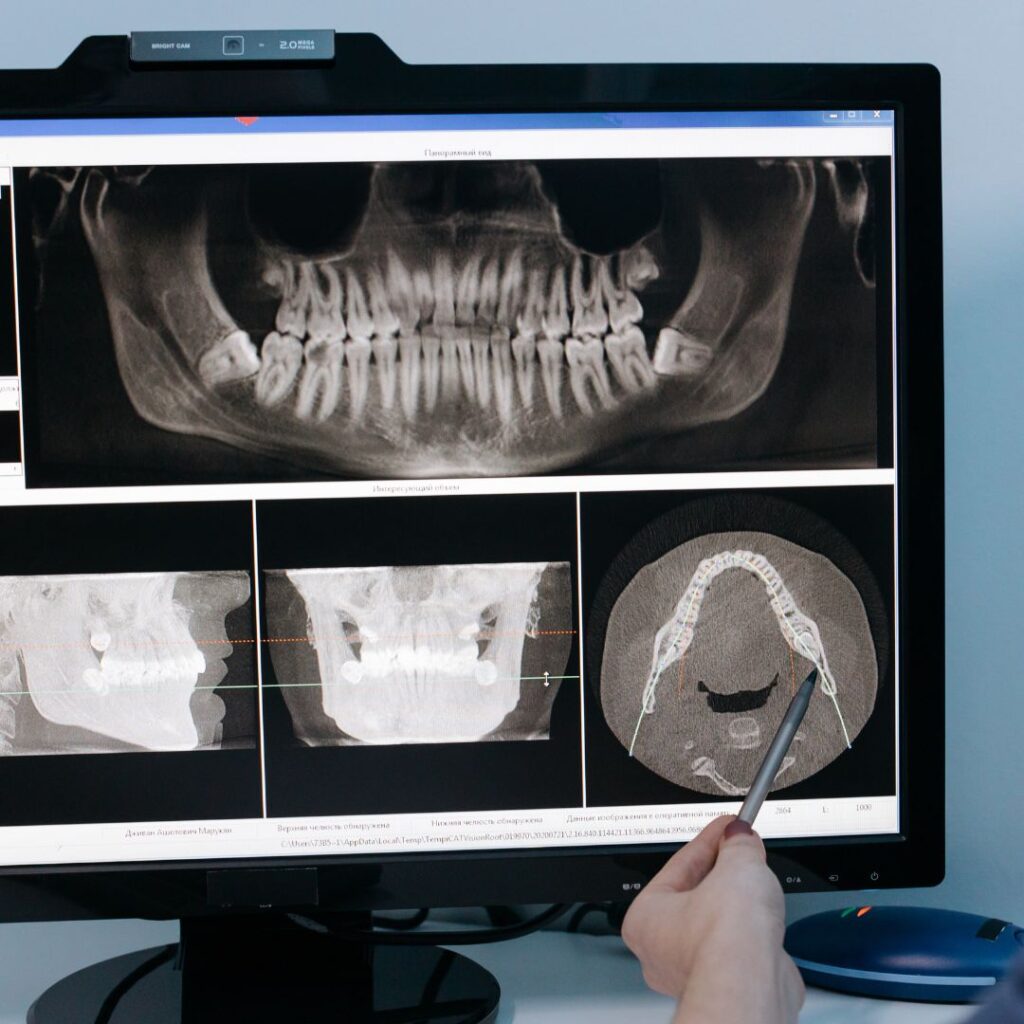

El CBCT dental es un sistema de tomografía computarizada de haz cónico que permite obtener imágenes tridimensionales de alta definición de:

• Dientes

• Hueso maxilar y mandibular

• Nervios dentales

• Senos maxilares

• Articulación temporomandibular (ATM)

A diferencia de una radiografía convencional en 2D, el tomógrafo CBCT 3D proporciona una visión completa en volumen, permitiendo analizar cada estructura desde todos los ángulos.

En otras palabras: vemos lo que antes no se podía ver con tanta claridad.